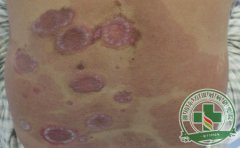

从银屑病图片了解银屑病治疗方法

许多人在发觉自己可能患有银屑病后,首位时间会上网搜索银屑病图片,看看自己的症状是否与图片类似,今儿寻求银屑病治疗之法。这种方法虽然并不规范,但是有一定的帮助作用。银屑病治疗不能仅靠单纯的网络判断,更应...[详细]